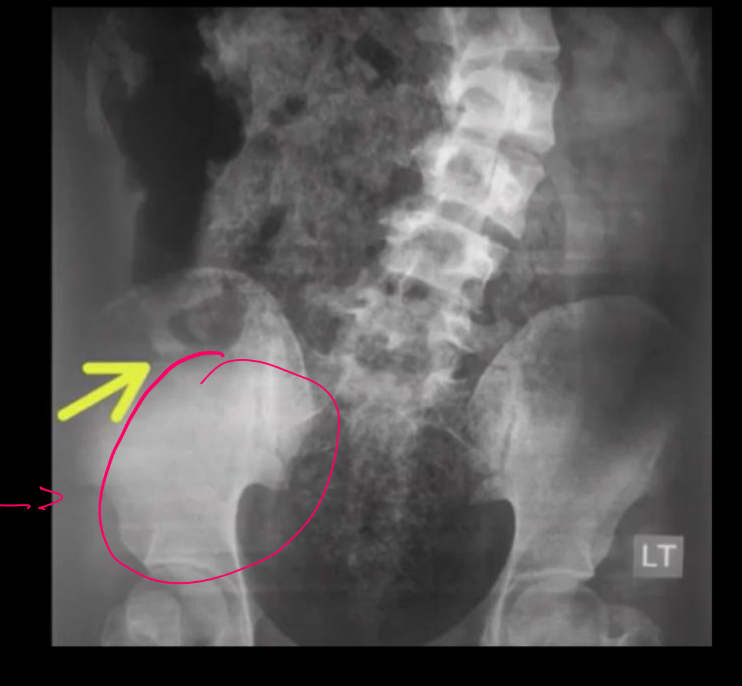

6

Que es eso

A

hiperdensidad articulación sacroiliaca drch